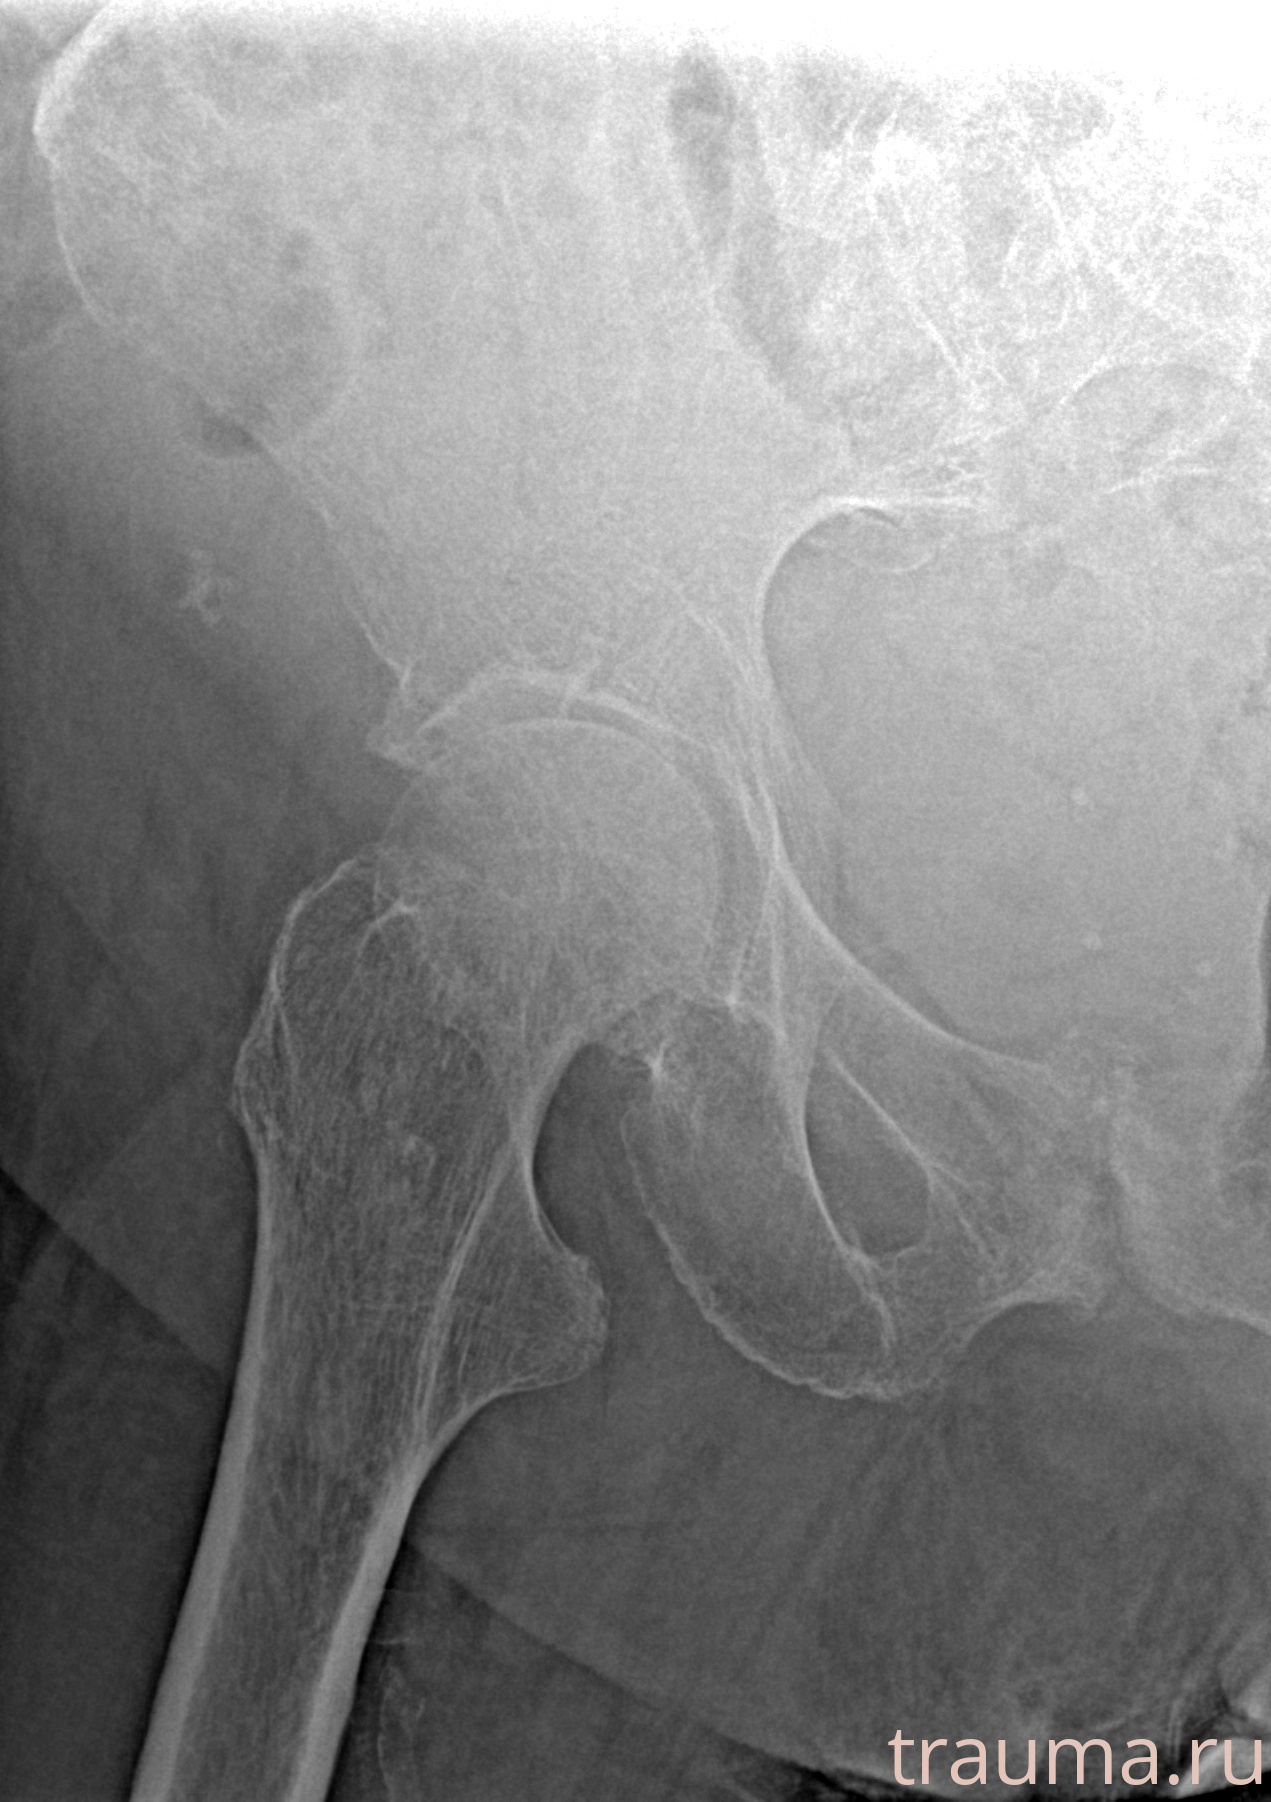

Рентгенограммы

Рентген на дому: по вашему адресу приезжает врач-рентгенолог, травматолог-ортопед с мобильным рентгеновским аппаратом, проводит диагностику травмы или заболевания, делает необходимые рентгенограммы, дает рекомендации по дальнейшему лечению. Получить качественные снимки в домашних условиях возможно благодаря уникальной методике, разработанной МосРентген Центром для института  Склифосовского